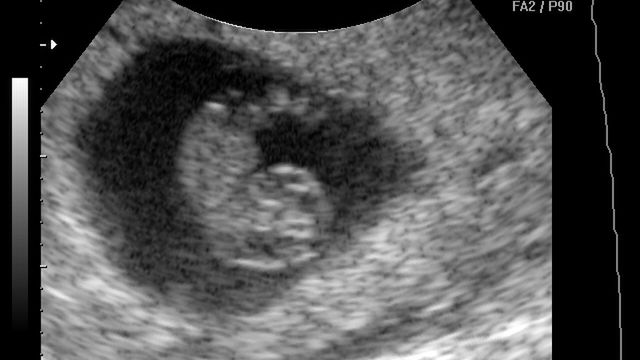

Płód w 8 tygodniu ciąży (zdjęcia)

/ 1Płód w 8 tygodniu ciąży - obraz USG

Kości płodu ulegają wydłużeniu, dzięki temu zarodek przybiera ludzkie kształty. Nerki zaczynają produkcję moczu

W 8 tygodniu przysadka mózgowa dynamicznie się rozwija dlatego jest już odpowiedzialna za produkcję hormonów i wzrost maluszka